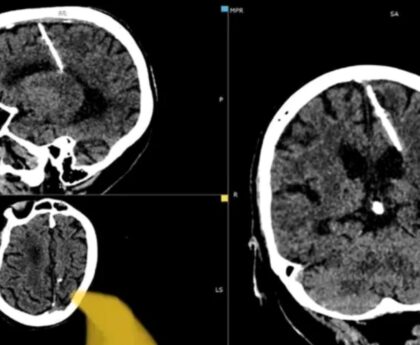

La scurt timp după incident, părinții băiatului au primit o concluzie preliminară din partea medicului legist. Deși rezultatele finale nu au fost încă disponibile, medicul a observat cu ochiul liber ceva neobișnuit la mușchiul inimii copilului, sugerând o posibilă afecțiune cardiacă. “Medicul legist a spus că nu i-a plăcut cum arăta mușchiul inimii”, a declarat instructorul Claudiu Pirtea.

Hadrian Borcea, medicul șef UPU SMURD Bihor, a explicat că, deși băiatul părea sănătos, anumite afecțiuni ascunse pot trece neobservate atât de părinți, cât și de personalul medical. Deși Filip primise o adeverință de la medicul de familie care atesta că este apt pentru activități sportive, instructorul subliniază importanța unor controale medicale mai riguroase. “Adeverințele nu ar trebui eliberate superficial. Analizele trebuie făcute corect”, a adăugat el.

În ultimii ani, numărul cazurilor de moarte subită în rândul copiilor, în timpul activităților sportive, a crescut alarmant. Specialiștii subliniază necesitatea unor controale medicale mai amănunțite înainte de implicarea copiilor în activități sportive. Adrian Tirla, medic specialist în medicină sportivă, recomandă efectuarea unui examen de specialitate, inclusiv un EKG de repaus, pentru a detecta eventualele afecțiuni care ar putea pune viața în pericol.

În prezent, medicii legiști continuă investigațiile pentru a stabili cu exactitate dacă băiatul avea o anomalie cardiacă care a dus la deces. Acest caz tragic subliniază importanța monitorizării atente a sănătății copiilor implicați în activități sportive.